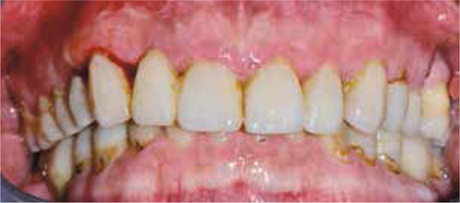

Bij het extraoraal onderzoek zie ik een lichte hypertrofie van de m. masseter. Intraoraal tref ik een ernstig versleten dentitie aan waarbij de slijtage niet passend bij de leeftijd kan worden genoemd (afbeelding 2-7 en tabel 1) .

Afb. 1

De heer H. bij de intake.

Afb. 2

Frontaal aanzicht van de dentitie.